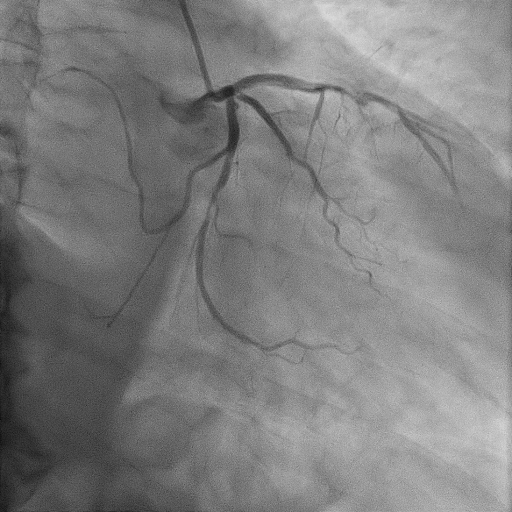

Relevant Catheterization Findings

The coronary angiography revealed normal and short left main coronary artery. The proximal to mid left anterior descending artery had severe stenosis of 90% with thrombus. The proximal segment of diagonal 1 had 80% stenosis. The proximal and distal left circumflex artery showed 50% and 80% stenosis respectively. The right coronary artery showed mild lesion of 20-30% at mid segment. The posterior left ventricular artery showed moderate stenosis of 50% at mid segment.

We proceeded with delayed selective PCI to the left anterior descending artery (LAD). The left main coronary artery (LMCA) was engaged with guiding catheter Medtronic Launcher 6FR EBU 3.5. The PTCA guide wire Shun R (SHUNMEI Medical) crossed the lesion with ease. Besides, we wired the diagonal 1 with PT2 (Boston Scientific) to provide side branch protection. The proximal to mid segment of the LAD lesion was pre-dilated with Sapphire NC 24 PTCA balloon 3.0x15mm and inflated to 12 atm. The lesion was stented with Xience Xpedition 3.0x48mm and inflated to 10atm. The stent was post-dilated with NC Trek balloon 3.5x12mm and inflated to 14atm. Noted while retracting the balloon during post-dilatation, the guiding catheter advanced deep into the LMCA several times. Subsequently, patient became progressively hemodynamically unstable. Trial of aspiration with Genoss Extractor but no thrombus was aspirated. Intracoronary Tirofiban bolus was administered. Unfortunately, patient went into cardiorespiratory arrest and intensive resuscitation was commenced. Angiography showed severe flow-limiting type D dissection of the LMCA. We proceeded with rescue stenting of LMCA with Xience Sierra 3.5x38mm with inflation to 12atm. The stent was post-dilated with NC Euphora 4.0x8mm and inflated to 18atm. The final result was TIMI flow 3 but the stent was about 3 to 5 mm proximal to the LMCA ostium. An intra-aortic balloon pump was also inserted and patient required 4 inotropes.